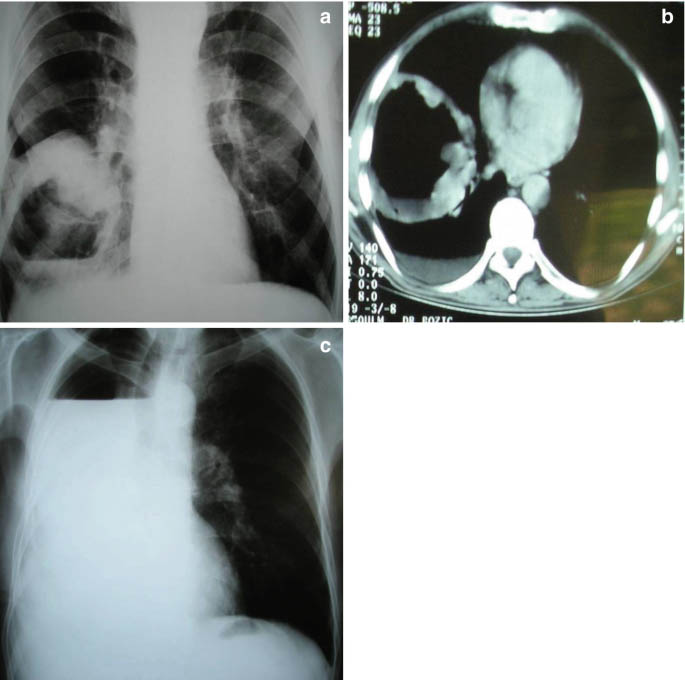

Entamoeba histolytica là tác nhân gây ra bệnh amip và gây ra các biểu hiện trong ruột và ngoài ruột bao gồm cả amip gan và amip phổi. Ước tính có 7 - 20% bệnh nhân mắc amip gan và 2 - 3% bệnh nhân mắc bệnh nghiêm trọng và có tính xâm lấn cũng bị tràn dịch màng phổi, áp xe phổi hoặc u nang phổi.

Hình Áp xe phổi do amip Entamoeba histolytica

Amip cũng đã được phát hiện gây ra bệnh mủ màng phổi và tắc nghẽn động mạch cảnh.